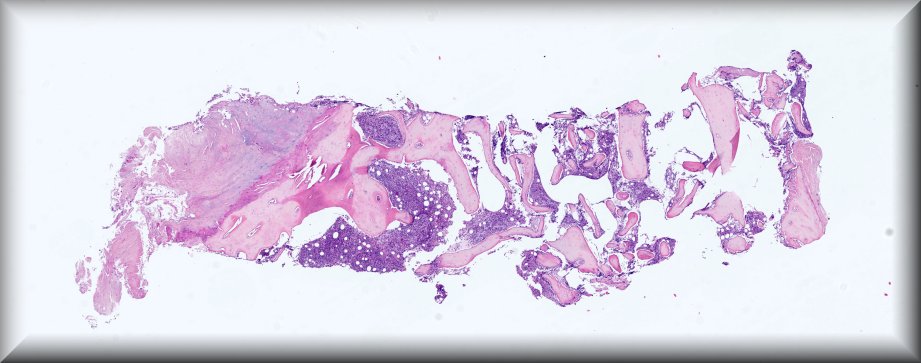

Caso 1.- María José Naharro Gascón, Julieta Romina Arbat, Elizabeth Burch Nchama, Amparo Taverner Lino, Encarna Marti Ibor, Maria Luisa Pérez Ebri.

Hospital Doctor Peset de Valencia.

Varón de 44 años que consulta por múltiples adenopatías en regiones inguinal y pélvica, que en el estudio PET-TC muestra captación e hipermetabolismo en esternón y escápula en relación a posible infiltración de médula ósea. Además, presenta en rodilla derecha a nivel cutáneo una lesión nodular indurada y violácea, de 1 cm de tamaño. No presenta afectación del estado general ni síntomas B. En el estudio por sospecha de neoplasia hematológica se realiza biopsia de médula ósea.